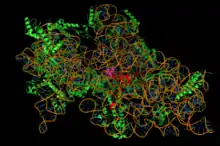

Inhibition de la synthèse protéique

La synthèse des protéines est un processus essentiel des cellules vivantes. L'acteur central de ce processus dans lequel l'ARN messager est traduit en protéine est le ribosome, l'organite cellulaire qui est responsable de cette étape. Les détails du mécanisme de traduction et les ribosomes des bactéries sont sensiblement différents de ceux des eucaryotes. Il existe un grand nombre de molécules antibiotiques qui exploitent ces différences et sont capables de bloquer sélectivement la traduction des protéines chez les bactéries, mais pas chez l'humain ou l'animal.

De fait, approximativement la moitié des antibiotiques utilisés en thérapeutique (disposant de l'AMM) ont pour cible le ribosome bactérien. Ces antibiotiques se répartissent en plusieurs classes, de nature chimique et de mode d'action différents. La plupart interagissent avec l'ARN ribosomique. Enfin, certains antibiotiques bloquent la traduction en inhibant l'action des facteurs de traduction associés au ribosome.

- Les aminoglycosides ou aminosides (exemples : streptomycine, gentamicine, amikacine) se fixent sur la petite sous-unité des ribosomes (30 Svedberg) au niveau du site du décodage des codons, empêchent la traduction de l’ARNm et conduisent à des erreurs de lecture.

- Les phénicols (exemples : chloramphénicol, thiamphénicol) bloquent la formation de la liaison peptidique. Ils se fixent sur la grande sous-unité du ribosome bactérien (50 Svedberg) mais pas sur celle des ribosomes eucaryotes.

- Les cyclines (exemples : tétracycline, doxycycline, auréomycine) : en se fixant sur la sous-unité (30 S), elles bloquent l’élongation de la chaîne polypeptidique.

- Les macrolides et kétolides (exemples : érythromycine, azithromycine) agissent sur la partie 50 S du ribosome et bloquent l’élongation de la chaîne polypeptidique.

- La puromycine mime l’extrémité d’un ARNt, prend sa place dans le ribosome et bloque l’élongation de la chaîne polypeptidique.

- L'acide fusidique bloque l'action du facteur de traduction EF-G qui permet la translocation (progression) du ribosome sur l'ARN messager.